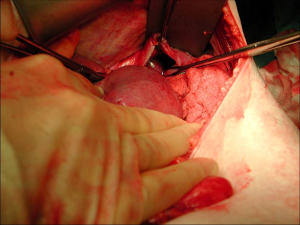

הטיפול בקרעים בסרעפת הוא כירורגי. הגישה היא בדרך כלל בטנית, עקב השיעור הגבוה של חבלות בטניות נלוות בפציעות מסוג זה. רוב הקרעים מתרחשים בצד השמאלי של הסרעפת, מכיוון שבצד הימני הכבד מגן על הסרעפת בפני חבלה קהה. לאחר פתיחת הבטן וזיהוי הקרע תופרים את הסרעפת בתפרים שאינם נספגים (תמונות).

| תמונה 5.16: קרע בסרעפת ותפירתה. עליון ימין רואים את הקרע, עליון משמאל חשיפת הקרע. תחתון תפירת הקרע | |